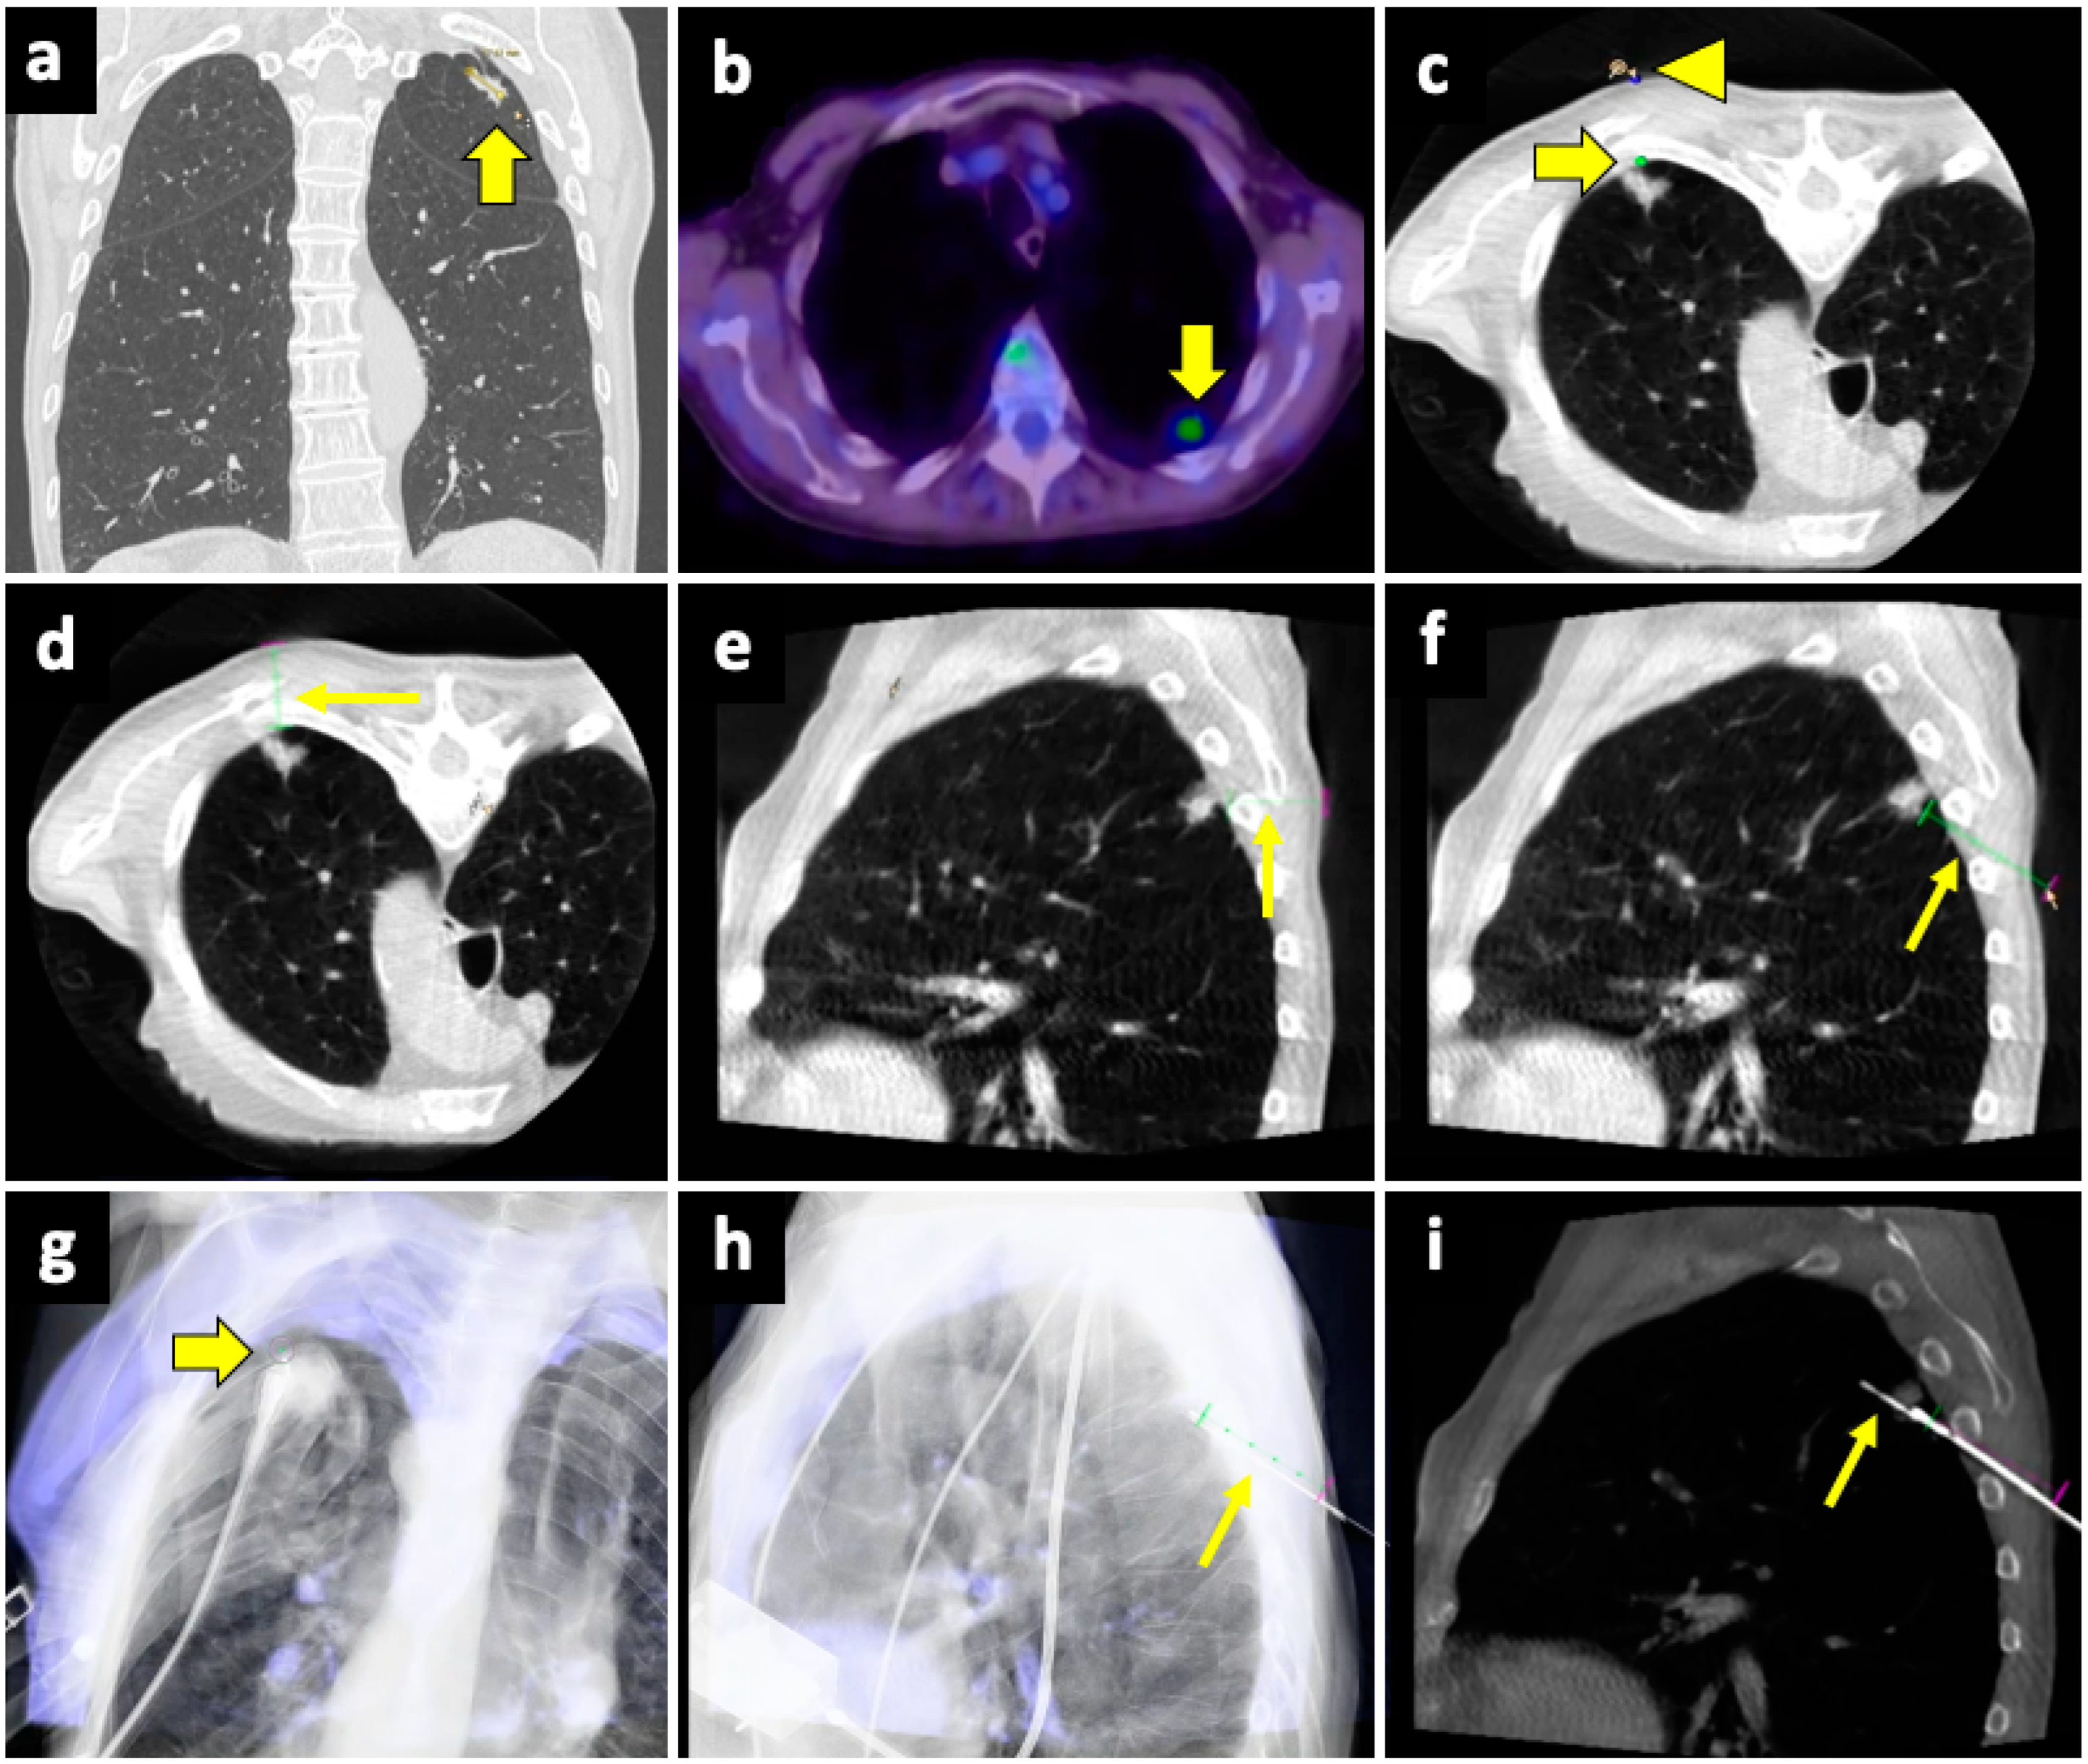

The CBCT system consists of flat-panel fluoroscopy and a CBCT scanner. The execution of CBCT-virtual-navigation-guided lung biopsy is performed in steps. The first step is to acquire a CBCT scan for adequate planning of the biopsy. Briefly, using the software (various software exist, by different vendors), the operator establishes the target lesion and the needle entry point at the skin surface, after which a virtual segment connecting the entry and target points is shown, representing the needle path. On the basis of this planning, the software automatically calculates the correct C-arm position to display the needle entry point on the patient’s skin. This phase of the procedure is called “entry point positioning”. After skin disinfection of the access area, under fluoroscopic guidance, the operator positions the needle tip at the cutaneous entry point, based on the CBCT image appearing on the monitor as a fusion of the 3D volume previously acquired using CBCT and the real-time fluoroscopy bidimensional plane. At this time, the C-arm rotates in the “progression view” position, perpendicular to the previous one. Then, the needle is advanced into the chest to reach the target point, following the virtual path previously determined and displayed on the monitor in real-time fluoroscopy. Then, a second CBCT scan is performed to verify the needle’s correct placement, and the biopsy is taken. A final scan is acquired to assess any complications [124]. An example of CBCT-guided biopsy is illustrated in Figure 4.

Figure 4.

Biopsy, pneumothorax, and manual aspiration. (a) A left upper lobe solid lesion (thick arrow) is detected in a 77-year-old man with COPD. (b) The lesion demonstrates FDG avidity at the PET-CT exam (thick arrow), and the tumor board gave instruction to simultaneously conduct biopsy and ablation, which were performed under CBCT guidance. (c) After acquiring the first CBCT scan, the target point (thick arrow) and the entry point (arrowhead) are selected at the workstation using the dedicated software (Philips XperGuide). (d) A virtual trajectory (thin arrow) is created between the target and entry points; note that the axial trajectory passes through the scapula and a rib in the axial view. (e) The impossibility of using an axial trajectory (thin arrow) is also confirmed in the sagittal view. (f) The entry point is changed, and the new oblique virtual trajectory (thin arrow) now passes through intercostal space. (g) The established virtual trajectory is displayed over the real-time fluoroscopic images in the “entry point” view, in which the entry and target points correspond (thick arrow); this view is used in this case to introduce the devices (microwave antenna and coaxial needle system) from the skin towards the target. (h) Visualization can occur also in a plane perpendicular to the prior one, the “progression” view, in which the virtual trajectory (thin arrow) can be seen at the maximum of its length; this view is used to check the progression of the devices along the established trajectory. (i) The Sagittal CBCT image shows the sample notch of a CNB system positioned at the level of the target lesion (thin arrow). The lesion was then biopsied (histology: lung adenocarcinoma) and ablated. Abbreviations—CBCT: cone-beam-computed tomography; FDG: fluorodeoxyglucose; PET-CT: positron emission tomography-computed tomography.

This technique overcomes the limits of conventional CT, the lack of real-time monitoring during the puncture, and the lack of flexibility due to the forced choice of the axial plane [65,125,126], allowing for a real-time fluoroscopy visualization of the needle puncture and of the solid lesion movement due to respiration, as well as a free 3D rotation of the C-arm around the patient, leading to the best puncture path [127,128].

CBCT-virtual-navigation-guided lung biopsies are safe and accurate, with a high technical success rate (>99%) and high accuracy (>95%) [127,129]. Moreover, compared to conventional CT guidance, CBCT virtual navigation facilitates needle positioning and reduces the procedural time, the effective X-ray dose [125,129], and the incidence of complications [125]. Moreover, in solid lung lesions smaller than 15–20 mm, its accuracy was higher compared to conventional CT guidance (98.2% vs. 83.7%) [128]. Good results using CBCT guidance in small pulmonary nodules (<1 cm) were also reported by Choo et al., with sensitivity, specificity, and diagnostic accuracy of 96.7%, 100%, and 98%, respectively, with only a 6.5% rate of PNX and 5.6% of hemoptysis [130]. Using CBCT, no significant differences in sensitivity, specificity, and accuracy between the PTLB of nodules <1 cm and larger nodules (from 1 to 2 cm) were found [131].